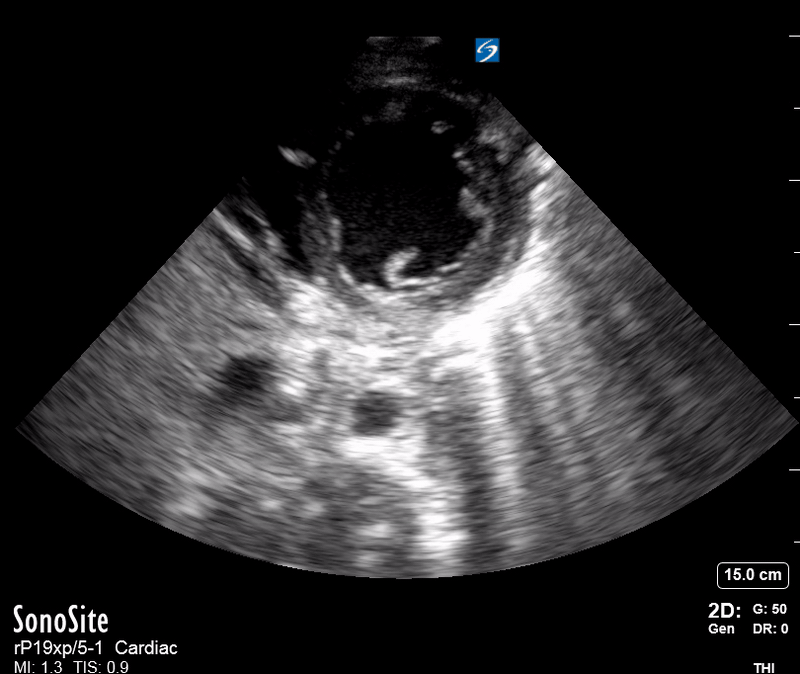

THE VIEWS

The PLAX view is versatile and allows the recognition of multiple landmarks, making it good for visual estimation of LV contractility. It is essential to optimize the view ensuring a true sagittal long axis, as being oblique to the LV chamber may underestimate its size and overestimate its emptying. The PSAX view at the level of the papillary muscles reveals the entire muscular circumference and concentric squeeze of the LV. It is useful to estimate both global function and focal wall motion abnormalities. The A4C view, although technically challenging, provides good insight into the global myocardial function and chamber size.

SIGNIFICANTLY IMPAIRED / DILATED LV

A severely depressed LV contractility, particularly when paired with a plethoric IVC or lung B-lines, indicates systolic heart failure. Chronically raised afterload can lead to severe dilation of the LV.

A “non-coordinated myocardial activity” can be recognised during cardiac arrest, and its prognosis is beyond poor.

HYPERDYNAMIC

In contrast, hyperdynamic states are associated with decreased afterload and are classically found in patients with sepsis or severe hypovolaemia. A hyperdynamic heart should be accompanied by a small, collapsing IVC. Moreover, is essential to remember that tachycardic is not the same as hyperdynamic, as the latter is a measure of contractile activity and emptying. A tachycardic heart is not necessarily hyperdynamic.